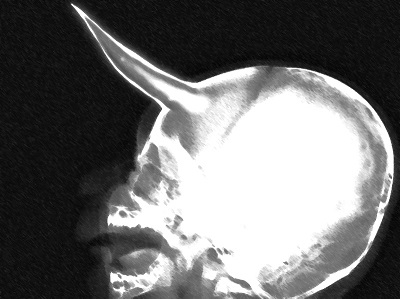

SCP-170-JP-h2头部X光片

12月31日20时许,3名隐栖生物室人员在京都市右京区爱宕山搜查时发现了持有上述的右前臂的SCP-170-JP-h个体。基金会人员到达现场时,该个体由于被隐栖生物室人员枪击而丧失生命体征,虽立即尝试进行了心肺复苏处理,但该个体仍在20时33分死亡。遗体被移交给基金会并被指定为SCP-170-JP-h2。SCP-170-JP-h2推测为13岁的女性,前额的角长度达到15cm。